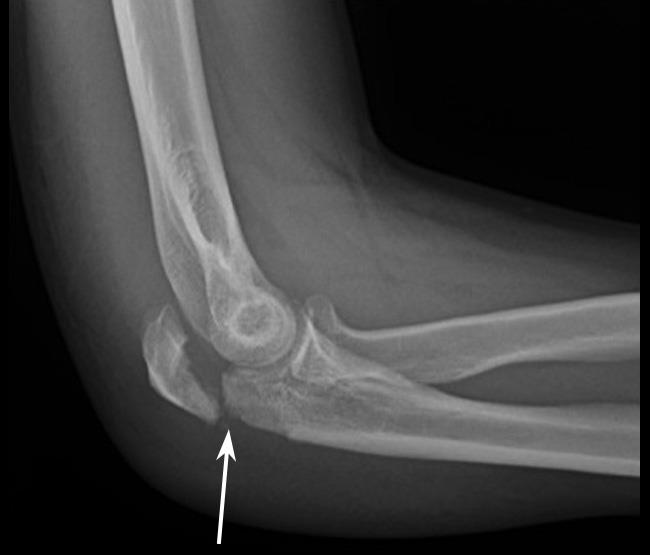

X-rays

X-rays provide images of dense structures, such as bones. Your doctor will order X-rays of your elbow to help diagnosis your fracture. Depending on your symptoms, the doctor may also order X-rays of your upper arm, forearm, shoulder, wrist, and/or hand to determine whether you have other injuries.

This X-ray taken from the side shows an olecranon fracture in which the pieces of bone have moved out of place (displaced).Reproduced from Konda SR: Fractures around the elbow, in Egol KA, Gardner MJ, eds: Let's Discuss Management of Common Fractures. Rosemont, IL, American Academy of Orthopaedic Surgeons, 2016, pp. 17-30.